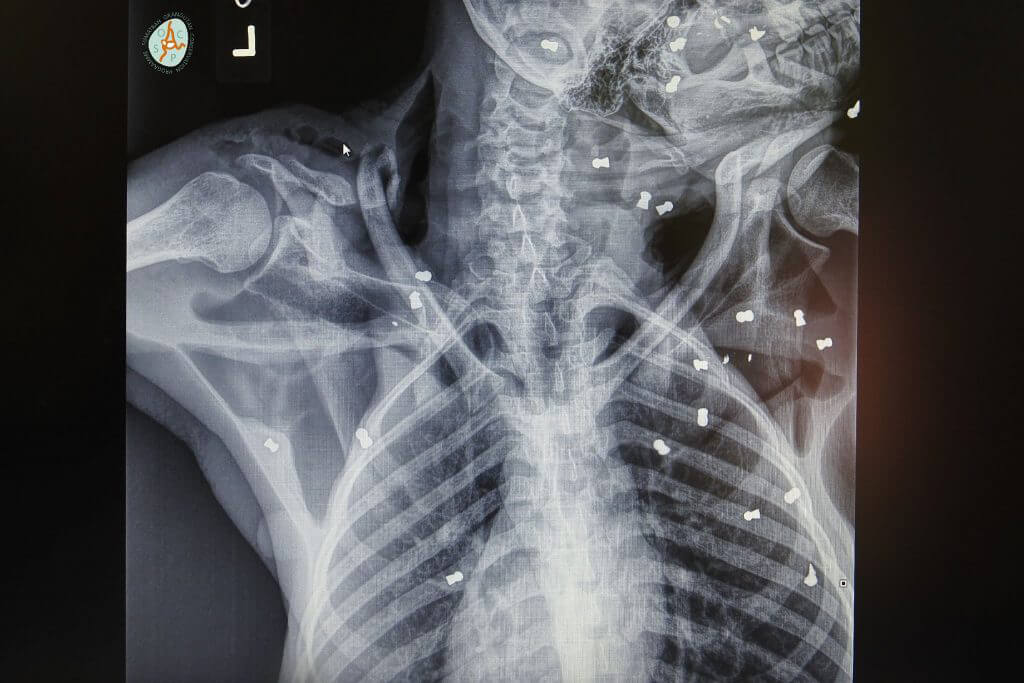

X-rays showed veterinarians the true horror of the mother orangutan’s injuries. She had been sprayed with 74 pellets throughout her body.

She had fractures on her legs and hands as well.